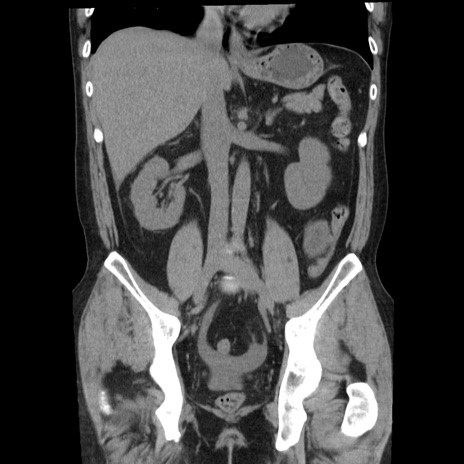

横断像